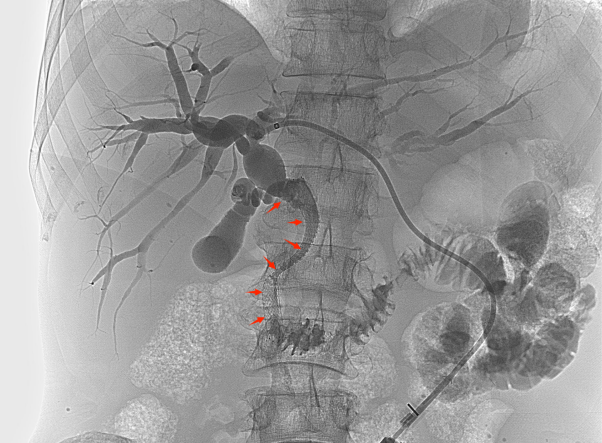

![]() 【如何治疗胆道梗阻?】 ![]() 胆道梗阻后,胆红素快速升高,会极大加重肝功能负担,最终导致肝功能衰竭。如何快速、有效的退黄成为梗阻性黄疸治疗的关键措施。介入治疗通过放置胆道引流管、胆道支架等手段能安全、高效退黄,以绝对微创的方式最大限度保护肝功能,为后续治疗创造机会。 ![]() ![]() 【经皮肝穿刺胆道引流术】 ![]() 在X线透视引导下穿刺扩张的肝内胆管并置入引流管,可以快速引流淤积的胆汁,减轻黄疸、保护肝功能,为后续治疗创造条件。优点在于见效快,能快速退黄和控制胆道感染。缺点在于需长期携带引流管并定期更换,生活质量降低,且胆汁无法进入肠道,影响消化功能。 ![]() ![]() ![]()

![]() 【经皮胆道支架置入术】 ![]() 胆道支架置入能很好地弥补经皮肝穿刺胆道引流术的不足之处,通过在胆管狭窄/阻塞处安置金属支架,解除胆道梗阻、恢复通畅,促进胆汁入肠,改善消化功能的同时无需长期带管,显著提高了生活质量,适合短期内有效解除胆道梗阻的患者(如恶性胆道梗阻)。 ![]() 低位胆道梗阻支架置入 ![]() 高位胆道梗阻支架置入 变身“小金人”并不可怕,找准病因,用对方法,也能轻松退黄。介入治疗应用于胆道梗阻多年,技术成熟,安全且高效。市四医院介入室能常规开展各类复杂胆道梗阻的介入治疗,高效扫“黄”,为肝功能保驾护航。